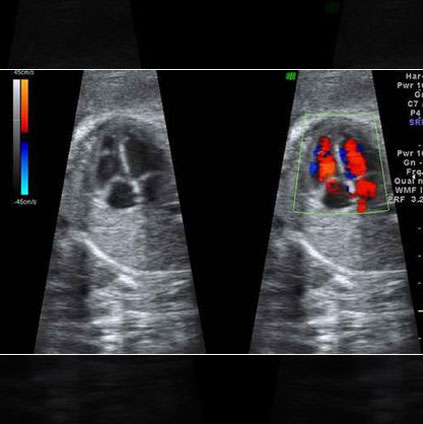

Fetal echocardiography ultrasound showing detailed color Doppler view of the baby’s heart to detect cardiac abnormalities during pregnancy